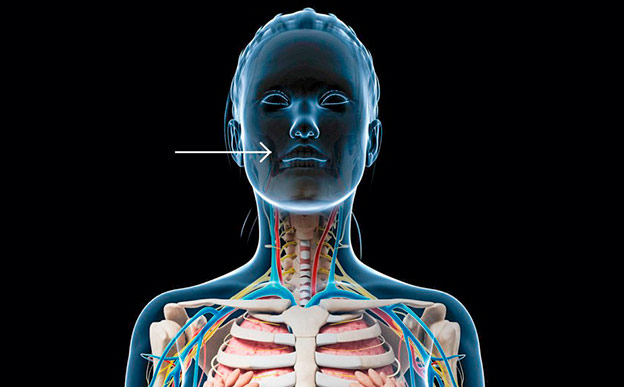

Las muelas del juicio

A menudo son problemáticas. A partir de ahí, la práctica de extraer los terceros molares se ha convertido en habitual en muchas consultas odontológicas. La opinión médica está dividida: frente a muchos ortodoncistas que optan por su extracción ‘para evitar recaídas’, las directrices europeas del Instituto Nacional para la Salud y la Excelencia Clínica señalan que solo deben extraerse cuando suponen un problema, pero no cuando el objetivo únicamente es la prevención.